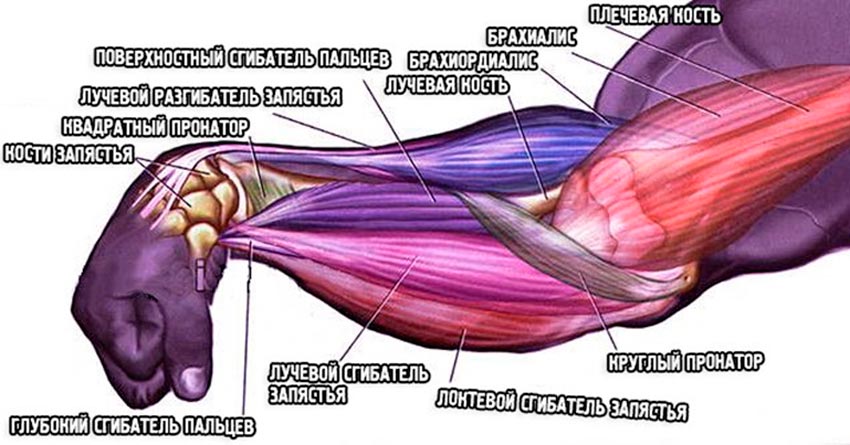

Анатомия и функции мышцы brachioradialis